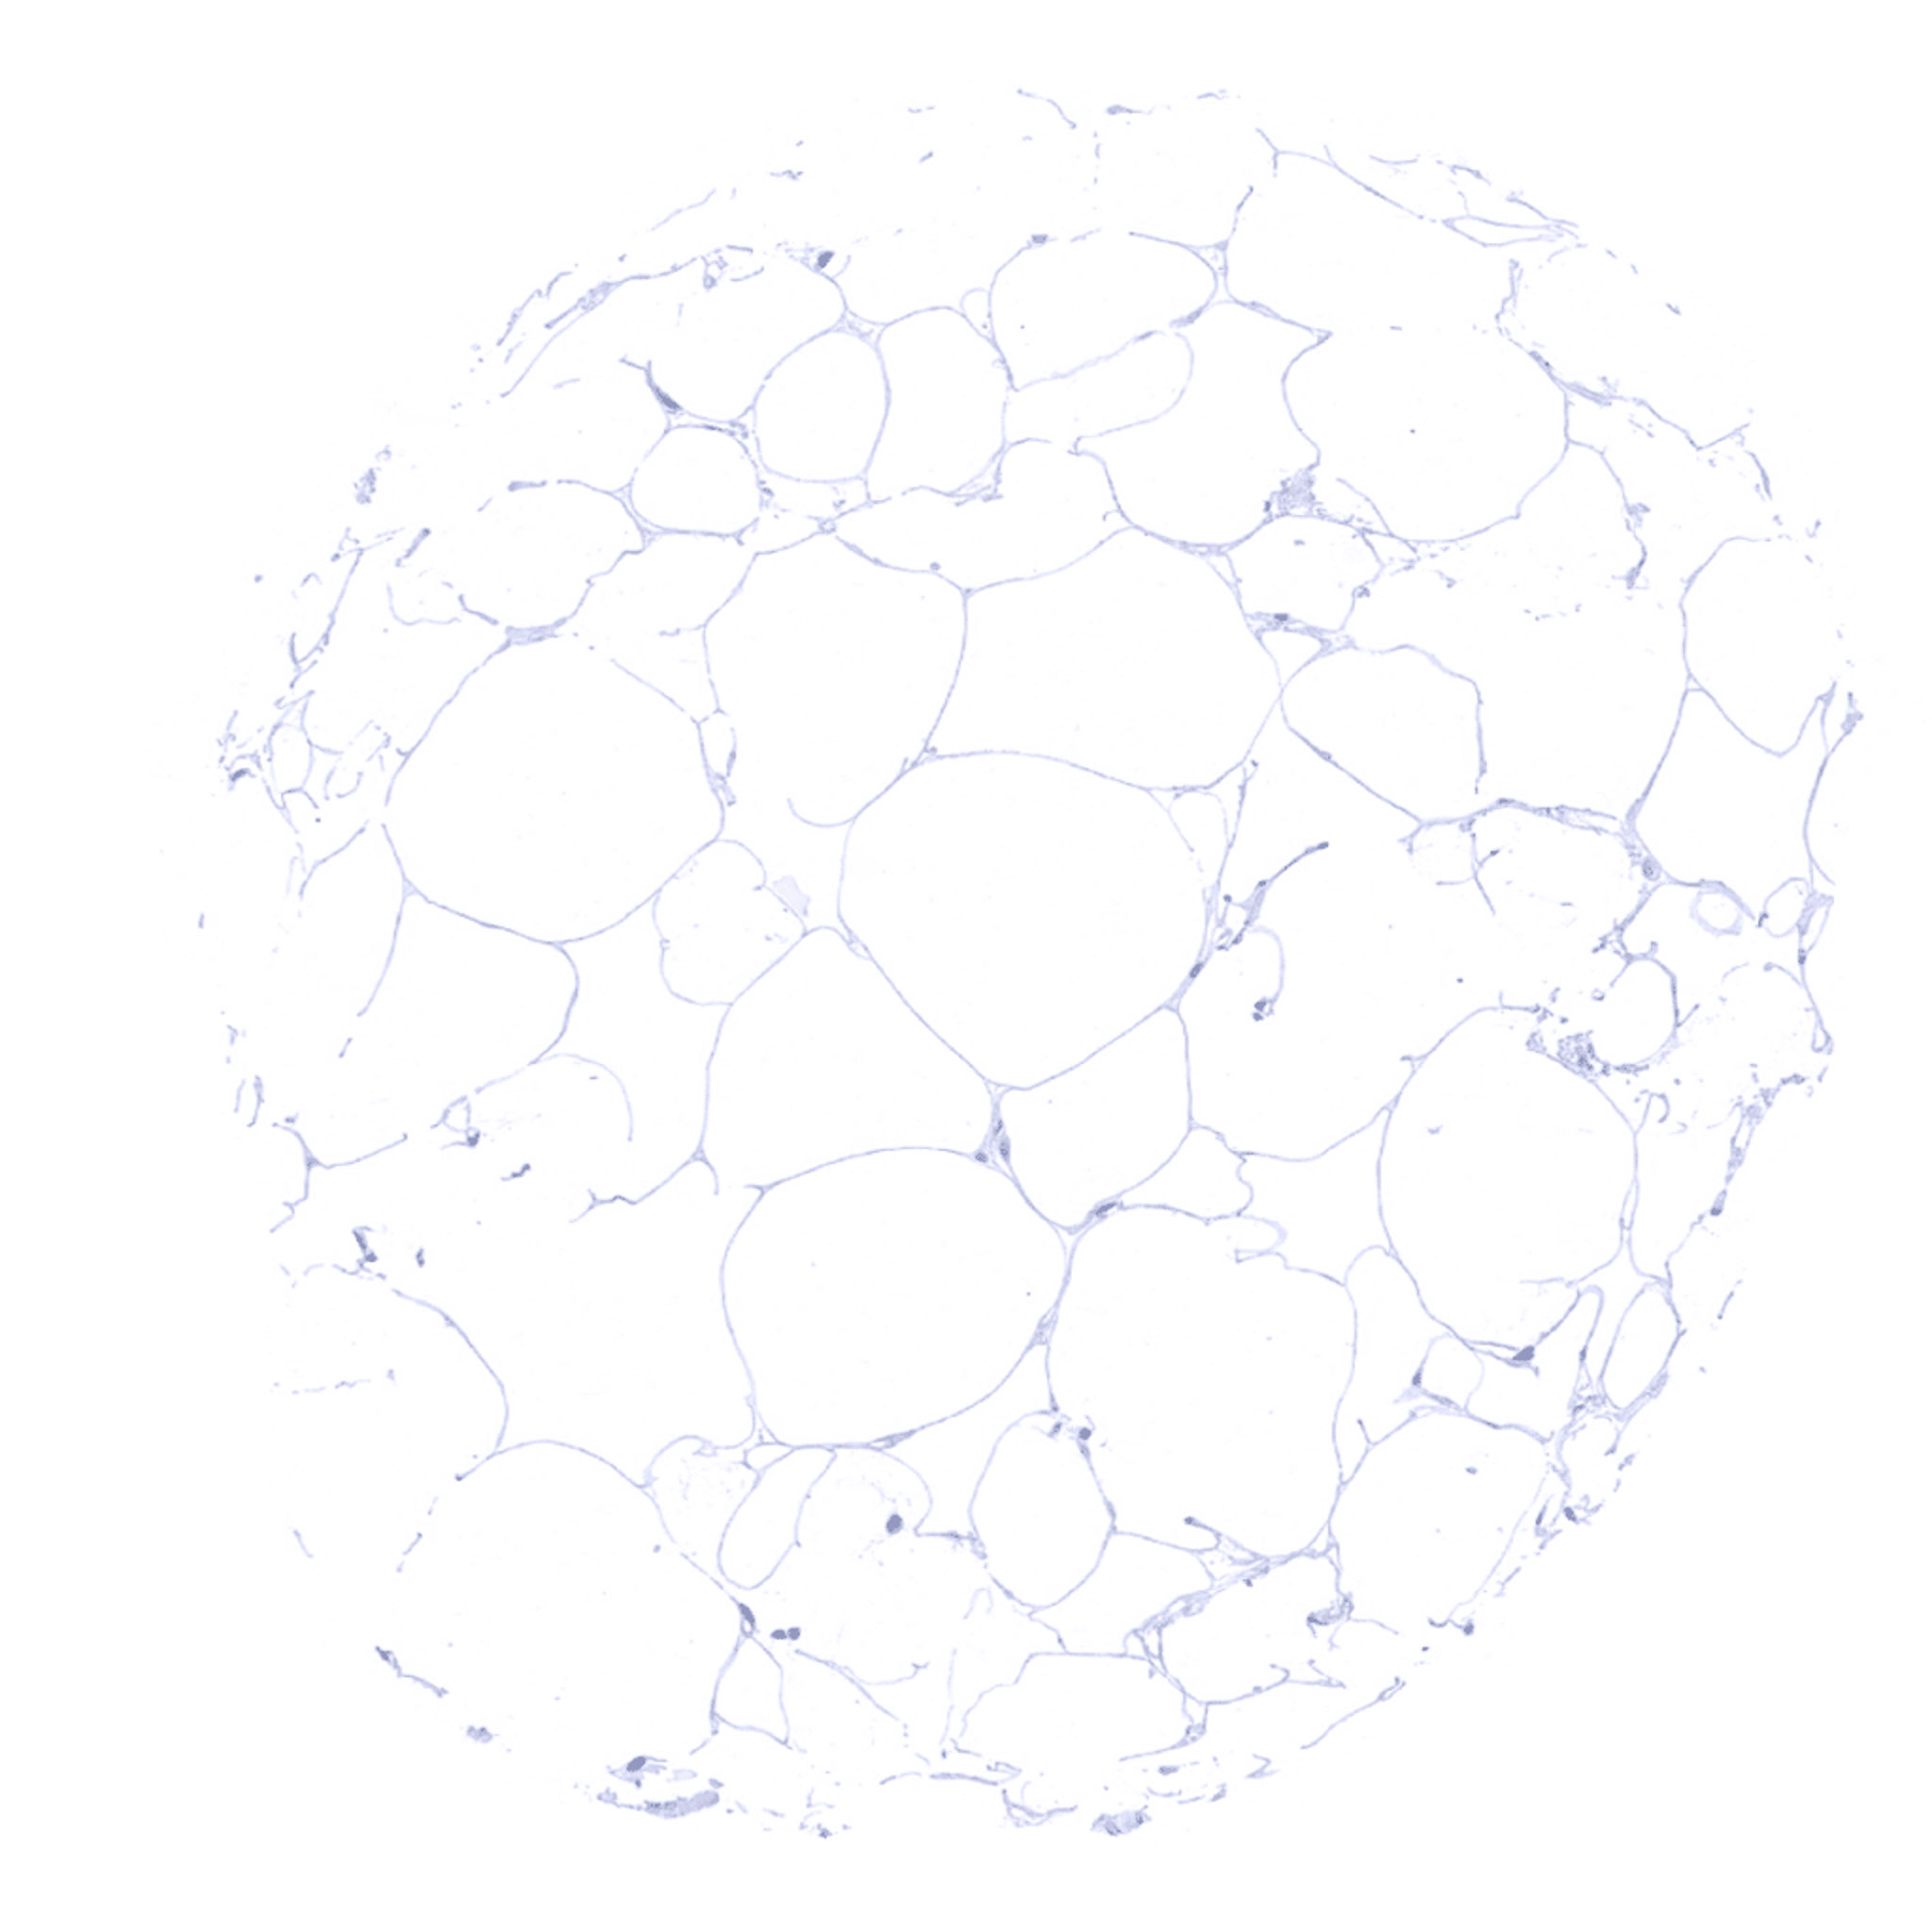

Fat

Parathyroid – Parathyroid gland showing intense cytoplasmic Parathyroid Hormone immunostaining of all glandular cells.

Parathyroid – Strong cytoplasmic Parathyroid Hormone immunostaining of all cells of a parathyroid gland.